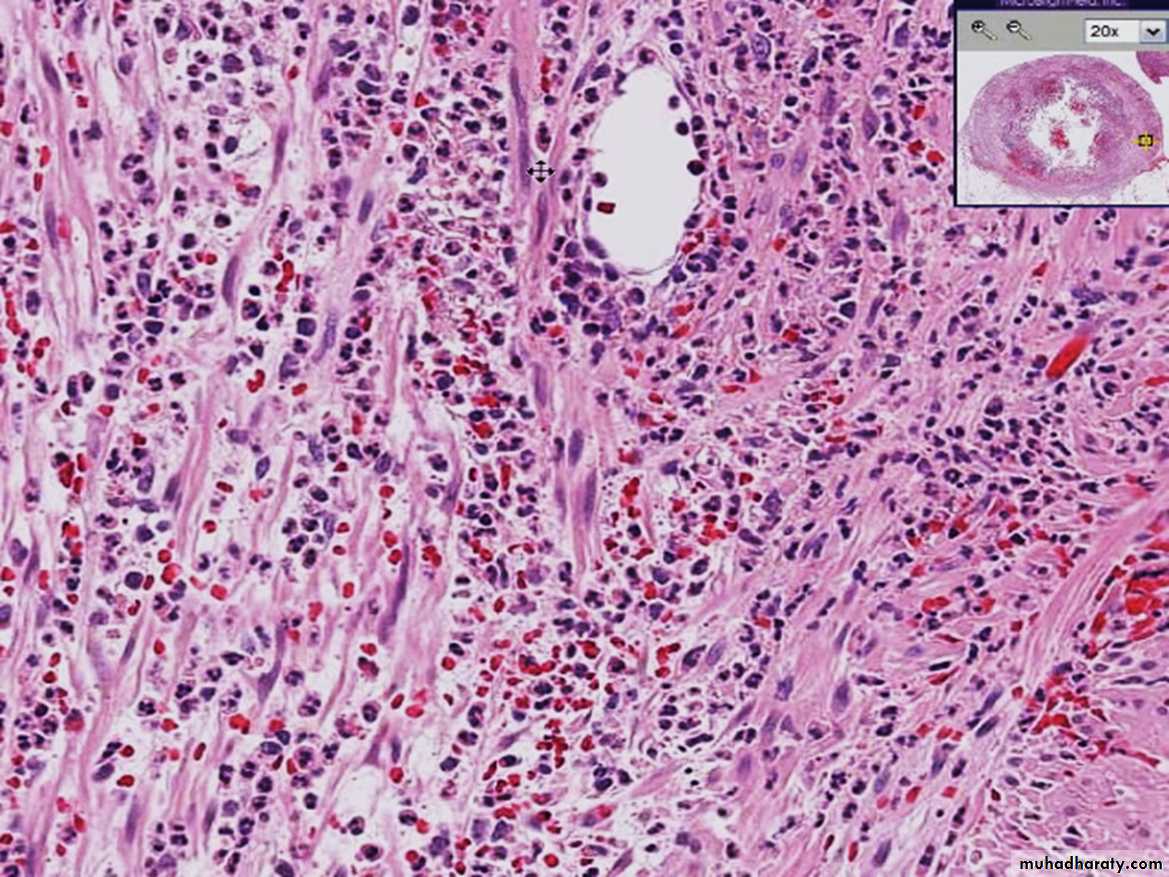

Acute appendix

Acute Inflammation